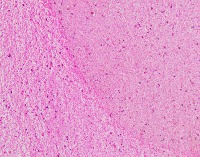

Medical Diagnostics: geckler5 can be used in healthcare facilities to analyze images of tissue samples, blood smear slides, or other medical images to detect the presence and distribution of White Blood Cells (WBC) and Erythrocyte Hemoglobin Concentration (EHC). This can aid in diagnosing diseases such as infections, anemia, or leukemia.

Research and Development: Scientists working in the field of hematology or immunology can use geckler5 to analyze large datasets of blood samples in their research studies. This can help them better understand blood cell morphology, variations, and concentrations in different conditions, ultimately leading to new medical discoveries.

Pharmaceutical Testing: The pharmaceutical industry can utilize geckler5 to analyze the effects of new drugs or treatment methods on WBC and EHC levels. This would allow researchers to monitor the efficacy, side effects, and other critical factors for drug trials and approval processes.

Educational Purposes: Educational institutions teaching medical or biological courses can implement geckler5 as a learning tool, helping students to identify and differentiate between various blood components. This can enhance their understanding of blood cell compositions and related medical conditions.

Blood Donation Centers and Blood Banks: geckler5 can be employed to assess the quality of blood donations in terms of WBC and EHC levels. This automated analysis would help staff ensure that donated blood meets necessary standards and is safe for transfusion into patients.